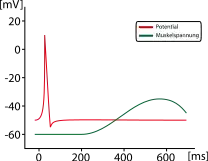

| Response to stimulus |  |

|

|